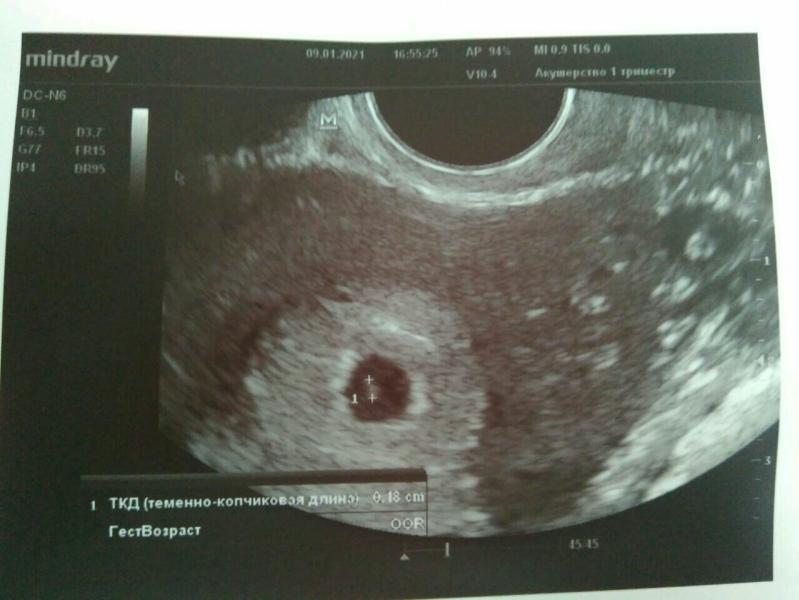

Повторюсь, 5 января я узнала о беременности и начала метаться в дальнейших действиях. Сначала записалась в Гемотест на ХГЧ, потом подумала и решила лучше сразу на узи пойти (хгч в итоге не сдавала вообще). У меня был нерв на тему маточная/нематочная, хотелось узнать этот момент. Я выждала 4 дня и на сроке ровно 5 недель попала на узи. Меня успокоили, что беременность маточная, малышок уже 1,8 мм😍 (фото 1). Мы с мужем подумали и решили за...